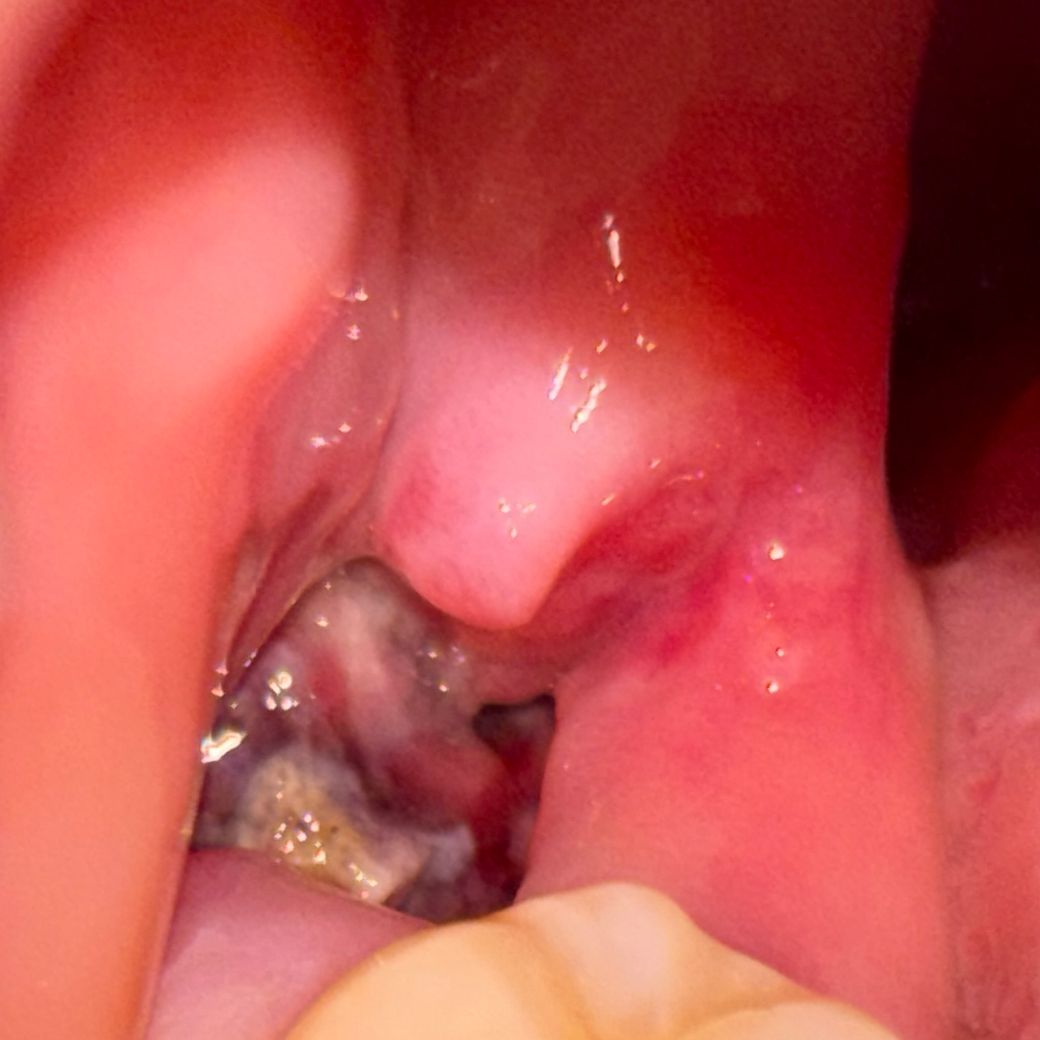

사랑니 발치한지 1주일되는날인데 드라이소캣일까요?ㅠㅠㅠㅜㅠ

혈병은 잘 있는듯한데 사진처럼 흰막같은게 조금 군데군데 있고, 입을 크게 벌려먹을때 아프더라고요ㅠ 가만히 있을땐 안 아프더라구요? 근데 보통 일주일 지나면 안 아프지않나요? 전에 뽑았을땐 잇몸차오를때까지 쭉 통증이 없었는데 이번에 뽑은건 왜 이럴까요? 치과왈 저번껏보다 뼈를 더깎았다고했나? 그래서 저번보다 더 아플꺼라고했었긴했는데 드라이소캣? 그런거면어쩌죠? 병원을 가봐야할까요?ㅠㅠ

드라이 소켓은 감염의 일종으로 통증이나 냄새가 심하게 납니다. 통증이 없다면 크게 걱정은 안하셔도 될것같습니다.

1. 뼈를 많이 쳤으면 통증과 부종은 더 오래갈 수 있습니다

2. 드라이소켓 양상은 아닐것 같습니다 걱정마세요